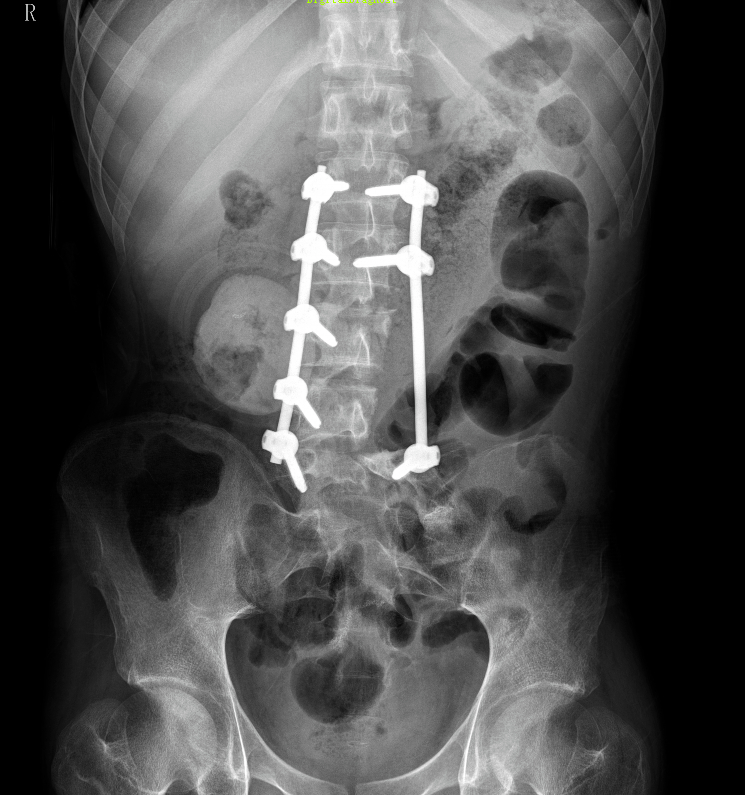

术前影像资料提示:患者左侧腹膜后存在一巨大恶性神经鞘瘤,最大径达20.1厘米。肿瘤已广泛侵犯周围结构,包括同侧髂骨、腰椎以及输尿管。

术后X线